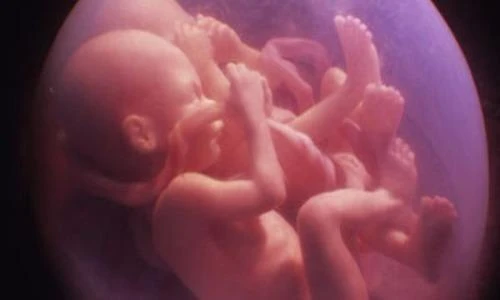

Với những trường hợp sinh ba trở nên, mổ đẻ thường là bắt buộc vì hiếm khi nào cả ba bé đều có thể quay đầu trong bụng mẹ một cách hoàn hảo được.

Những bé con sinh đôi nằm trong bụng mẹ với rất nhiều tư thế... buồn cười.

Thậm chí, các bé còn đạp nhau giành chỗ trong không gian chật hẹp.

Mặc dù vậy, ai cũng phải công nhận rằng các cặp sinh đôi khi ra đời đều trông rất đáng yêu.